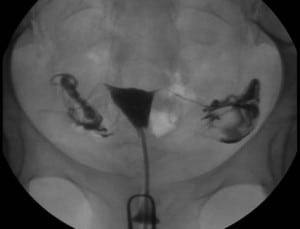

הדמיית הרחם והחצוצרות תחת שיקוף באולטרסאונד ללא כל קרינה וללא כאבים התחליף לצילום רחם ללא צורך בשיקוף בדיקת EXEM

הצילום התבצע בחדר המצוייד בצילום רנטגן ובוצע על ידי הזרקת חומר ניגוד שומני דרך צוואר הרחם. הבדיקה נערכה תחת קרינת רנטגן ולעיתים הייתה כרוכה באי נוחות רבה למטופלת וכאב. נשים הרגישות ליוד המנעו מביצוע בדיקה זו.

כעת, לראשונה בישראל, נכנסה בדיקה חדשה, בדיקת EXEM,  שמהווה בשורה גדולה לאוכלוסייה זו ומהווה פריצת דרך בגישה הטיפולית בנשים עם הפרעות  פוריות. הבדיקה החדשה מבוצעת בחדר אולטרסאונד רגיל במרפאתנו, תחת הדמיית אולטרסאונד ללא כל  קרינה. היא מבוצעת בעזרת הזרקה של חומר הנקרא exem שאין לו תופעות לוואי ומאפשר הדגמת הרחם והחצוצרות לרופא המטפל. הפעולה מבוססת על הכנסת קטטר גמיש לרחם והזרקת חומר תחת הסתכלות במכדיר האולטראסאונד.

פרופ׳ דוד סוריאנו : "נשים רבות הסובלות מבעיית פוריות עקב אנדומטריוזיס, ניתוחים קודמים או דלקות אגניות נזקקות לבדיקה זו, סוף סוף ניתן לבצע בדיקה אבחנתית להדגמת חלל הרחם והחצוצרות ללא צורך בחשיפה לקרינת רנטגן וללא כאבים. בנוסף בדיקה זו עשוייה לשפר השגת הריון ספונטני עקב שטיפת החצוצרות אם כי יש צורך במחקר בנושא זה״